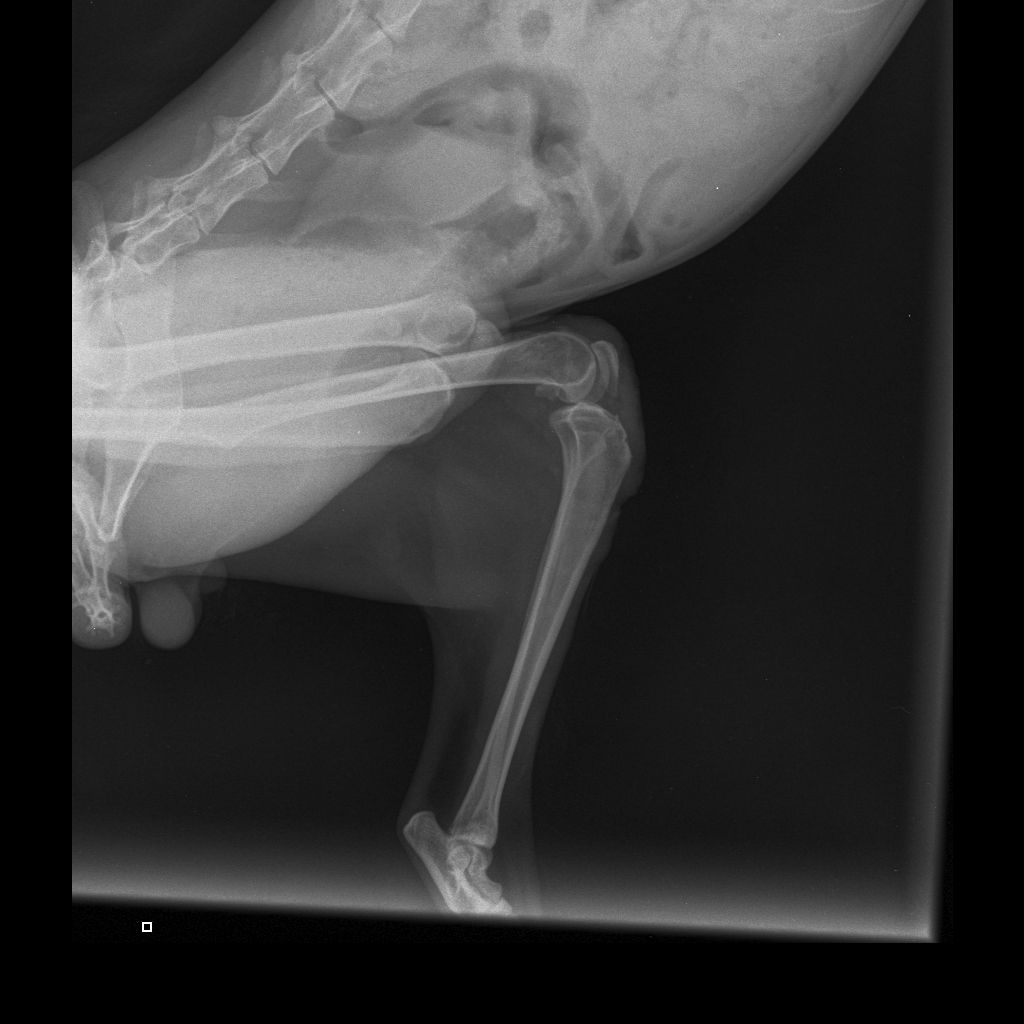

| История болезней/травм | 28.12.2025 - скальп кожи с бедра левой лапы и укол в колено. Где-то зацепился и потянул. Месяц так проходил, никто не помогал. Благодаря морозу заражения сильного не было. Обращение в ветклинику "КОТоПЁС": осмотр, стрижка, чистка раны солевым раствором, наложение повязки с лекарством (септо-спрей, бранолинд) и антибиотики (Кладакса, Марфлоксин) с обезболивающим, рентген. 29.12.2025 - Обращение в ветклинику "КОТоПЁС": осмотр, чистка раны солевым раствором, наложение повязки с лекарством (септо-спрей, бранолинд) и антибиотики с обезболивающим. 30.12.2026 - антибиотики. 31.12.2025 - Обращение в ветклинику "Эмили": чистка раны солевым раствором, наложение повязки с лекарством (септо-спрей, бранолинд) и антибиотики. 01.01.2026 - антибиотики. 02.01.2026 - чистка раны солевым раствором, наложение повязки с лекарством (септо-спрей, бранолинд) и антибиотики. 03.01.2026 - антибиотики. 04.01.2026 - Обращение в ветклинику "КОТоПЁС": осмотр, чистка раны солевым раствором, наложение повязки с лекарством (септо-спрей, бранолинд) и антибиотики, рентген. 05.01.2026 - антибиотики. 06.01.2026 - чистка раны солевым раствором, наложение повязки с лекарством (септо-спрей, бранолинд) и антибиотики. 07.01.2026 - антибиотики. 08.01.2026 - чистка раны солевым раствором, наложение повязки с лекарством (септо-спрей, бранолинд) и антибиотики. 10.01.2026 - Обращение в ветклинику "КОТоПЁС": осмотр, чистка раны солевым раствором, наложение повязки с лекарством (септо-спрей, бранолинд) и антибиотики. 11.01.2026 - антибиотики, глистогонка. 12.01.2026 - чистка раны солевым раствором, наложение повязки с лекарством (септо-спрей, бранолинд) и антибиотики. 13.01.2026 - чистка раны солевым раствором, наложение повязки с лекарством (септо-спрей, бранолинд) и антибиотики. 14.01.2026 - антибиотики. 15.01.2026 - антибиотики. 16.01.2026 - чистка раны солевым раствором, наложение повязки с лекарством (септо-спрей, бранолинд) и антибиотики. 17.01.2026 - антибиотики. 18.01.2026 - антибиотики. 19.01.2026 - чистка раны солевым раствором, наложение повязки с лекарством (септо-спрей, бранолинд) и антибиотики. 20.01.2026 - чистка раны солевым раствором, наложение повязки с лекарством (септо-спрей, Повязка мазевая Исполнение-Д4 50х70) и антибиотики. 23.01.2026 - чистка раны солевым раствором, наложение повязки с лекарством (септо-спрей, Повязка мазевая Исполнение-Д4 50х70). 26.01.2026 - чистка раны солевым раствором, наложение повязки с лекарством (септо-спрей, Повязка мазевая Исполнение-Д4 50х70). 29.01.2026 - чистка раны солевым раствором, наложение повязки с лекарством (септо-спрей, Повязка мазевая Исполнение-Д4 50х70) и антибиотики. 30.01.2026 - антибиотики. 31.01.2026 - чистка раны солевым раствором, наложение повязки с лекарством (септо-спрей, бранолинд) и антибиотики. 01.02.2026 - антибиотики. 02.02.2026 - чистка раны солевым раствором, наложение повязки с лекарством (септо-спрей, бранолинд) и антибиотики. 03.02.2026 - чистка раны солевым раствором, наложение повязки с лекарством (септо-спрей, бранолинд). 04.02.2026 - чистка раны солевым раствором, наложение повязки с лекарством (септо-спрей, бранолинд). 06.02.2026 - чистка раны солевым раствором, наложение повязки с лекарством (септо-спрей, ихтиоловая мазь). 07.02.2026 - чистка раны солевым раствором, наложение повязки с лекарством (септо-спрей, бранолинд). 09.02.2026 - чистка раны солевым раствором, наложение повязки с лекарством (септо-спрей, бранолинд). 11.02.2026 - чистка раны солевым раствором, наложение повязки с лекарством (септо-спрей, бранолинд). 12.02.2026 - чистка раны солевым раствором, наложение повязки с лекарством (септо-спрей, бранолинд). 14.02.2026 - чистка раны солевым раствором, наложение повязки с лекарством (септо-спрей, бранолинд). 15.02.2026 - чистка раны солевым раствором, наложение повязки с лекарством (септо-спрей, Повязка мазевая Исполнение-Д4 50х70). 17.02.2026 - чистка раны солевым раствором, наложение повязки с лекарством (септо-спрей, Повязка мазевая Исполнение-Д4 50х70). 19.02.2026 - чистка раны солевым раствором, наложение повязки с лекарством (септо-спрей, Повязка мазевая Исполнение-Д4 50х70). 20.02.2026 - чистка раны солевым раствором, наложение повязки с лекарством (септо-спрей, ихтиоловая мазь). 22.02.2026 - чистка раны солевым раствором, наложение повязки с лекарством (септо-спрей, ихтиоловая мазь). 24.02.2026 - чистка раны солевым раствором, наложение повязки с лекарством (септо-спрей, ихтиоловая мазь). 26.02.2026 - чистка раны солевым раствором, наложение повязки с лекарством (септо-спрей, ихтиоловая мазь). 28.02.2026 - чистка раны солевым раствором, наложение повязки с лекарством (септо-спрей, ихтиоловая мазь). 02.03.2026 - чистка раны солевым раствором, наложение повязки с лекарством (септо-спрей, ихтиоловая мазь). 03.03.2026 - чистка раны солевым раствором, наложение повязки с лекарством (септо-спрей, ихтиоловая мазь). 04.03.2026 - чистка раны солевым раствором, наложение повязки с лекарством (септо-спрей, ихтиоловая мазь). 06.03.2026 - чистка раны солевым раствором, наложение повязки с лекарством (септо-спрей, ихтиоловая мазь). 07.03.2026 - чистка раны солевым раствором, наложение повязки с лекарством (септо-спрей, ихтиоловая мазь). 08.03.2026 - чистка раны солевым раствором, наложение повязки с лекарством (септо-спрей, ихтиоловая мазь). 10.03.2026 - чистка раны солевым раствором, наложение повязки с лекарством (септо-спрей, ихтиоловая мазь). 12.03.2026 - чистка раны солевым раствором, наложение повязки с лекарством (септо-спрей, ихтиоловая мазь). 14.03.2026 - чистка раны солевым раствором, наложение повязки с лекарством (йод и солевой раствор, ихтиоловая мазь). 16.03.2026 - чистка раны солевым раствором, наложение повязки с лекарством (йод и солевой раствор, ихтиоловая мазь) и антибиотики. 17.03.2026 - антибиотики. 18.03.2026 - чистка раны солевым раствором, наложение повязки с лекарством (йод и солевой раствор, ихтиоловая мазь) и антибиотики. 19.03.2026 - глистогонка "Дирофен". 20.03.2026 - чистка раны солевым раствором, наложение повязки с лекарством (йод и солевой раствор, ихтиоловая мазь) и антибиотики. 22.03.2026 - чистка раны солевым раствором, наложение повязки с лекарством (йод и солевой раствор, ихтиоловая мазь). 24.03.2026 - чистка раны солевым раствором, наложение повязки с лекарством (йод и солевой раствор, ихтиоловая мазь). 26.03.2026 - чистка раны солевым раствором, наложение повязки с лекарством (йод и солевой раствор, Повязка мазевая Исполнение-Д4 50х70) и антибиотики. 27.03.2026 - антибиотики. 28.03.2026 - чистка раны солевым раствором, наложение повязки с лекарством (йод и солевой раствор, Повязка мазевая Исполнение-Д4 50х70) и антибиотики. 29.03.2026 - антибиотик 30.03.2026 - чистка раны солевым раствором, наложение повязки с лекарством (йод и солевой раствор, Повязка мазевая Исполнение-Д4 50х70) и антибиотики. 31.03.2026 - антибиотик 01.04.2026 - чистка раны солевым раствором, наложение повязки с лекарством (йод и солевой раствор, Повязка мазевая Исполнение-Д4 50х70). 04.04.2026 - чистка раны солевым раствором, наложение повязки с лекарством (йод и солевой раствор, ихтиоловая мазь). 06.04.2026 - чистка раны солевым раствором, наложение повязки с лекарством (йод и солевой раствор, Повязка мазевая Исполнение-Д4 50х70). 08.04.2026 - чистка раны солевым раствором, наложение повязки с лекарством (йод и солевой раствор, Повязка мазевая Исполнение-Д4 50х70). 10.04.2026 - чистка раны солевым раствором, наложение повязки с лекарством (йод и солевой раствор, Повязка мазевая Исполнение-Д4 50х70). 12.04.2026 - чистка раны солевым раствором, наложение повязки с лекарством (йод и солевой раствор, Повязка мазевая Исполнение-Д4 50х70). 14.04.2026 - чистка раны солевым раствором, наложение повязки с лекарством (йод и солевой раствор, Повязка мазевая Исполнение-Д4 50х70), глистогонка "Дирофен" и антибиотик (Кладакса). Заметно перестаёт кушать. 15.04.2026 - антибиотик (Кладакса). Плохо ест сам. 16.04.2026 - чистка раны солевым раствором, наложение повязки с лекарством (йод и солевой раствор, Повязка мазевая Исполнение-Д4 50х70) и антибиотик (Кладакса). 17.04.2026 - антибиотик (Кладакса). Ест только рыбку. 18.04.2026 - чистка раны солевым раствором, наложение повязки с лекарством (йод и солевой раствор, Повязка мазевая Исполнение-Д4 50х70) и антибиотик (Кладакса). 20.04.2026 - чистка раны солевым раствором, наложение повязки с лекарством (йод и солевой раствор, Повязка мазевая Исполнение-Д4 50х70). Принудительное кормление паштетом, пьёт сам. 22.04.2026 - чистка раны солевым раствором, наложение повязки с лекарством (йод и солевой раствор, Повязка мазевая Исполнение-Д4 50х70). Принудительное кормление паштетом, пьёт сам. 24.04.2026 - чистка раны солевым раствором, наложение повязки с лекарством (йод и солевой раствор, Повязка мазевая Исполнение-Д4 50х70). Принудительное кормление паштетом, пьёт сам. 26.04.2026 - чистка раны солевым раствором, наложение повязки с лекарством (мазь стрептоцид и солевой раствор, Повязка мазевая Исполнение-Д4 50х70). Принудительное кормление паштетом и водой. 28.04.2026 - чистка раны солевым раствором, наложение повязки с лекарством (мазь стрептоцид и солевой раствор, Повязка мазевая Исполнение-Д4 50х70). Принудительное кормление паштетом и водой. 30.04.2026 - чистка раны солевым раствором, наложение повязки с лекарством (йод и солевой раствор, ихтиоловая мазь). Принудительное кормление паштетом и водой. Обращение в ветклинику "ЭМИЛИ". 01.05.2026 - Обращение в ветклинику "ЭМИЛИ" - диагноз ФИП, откачка 300 мл жидкости из брюшной полости. Капельница и приём Коронакэт. 02.05.2026 - смерть. |